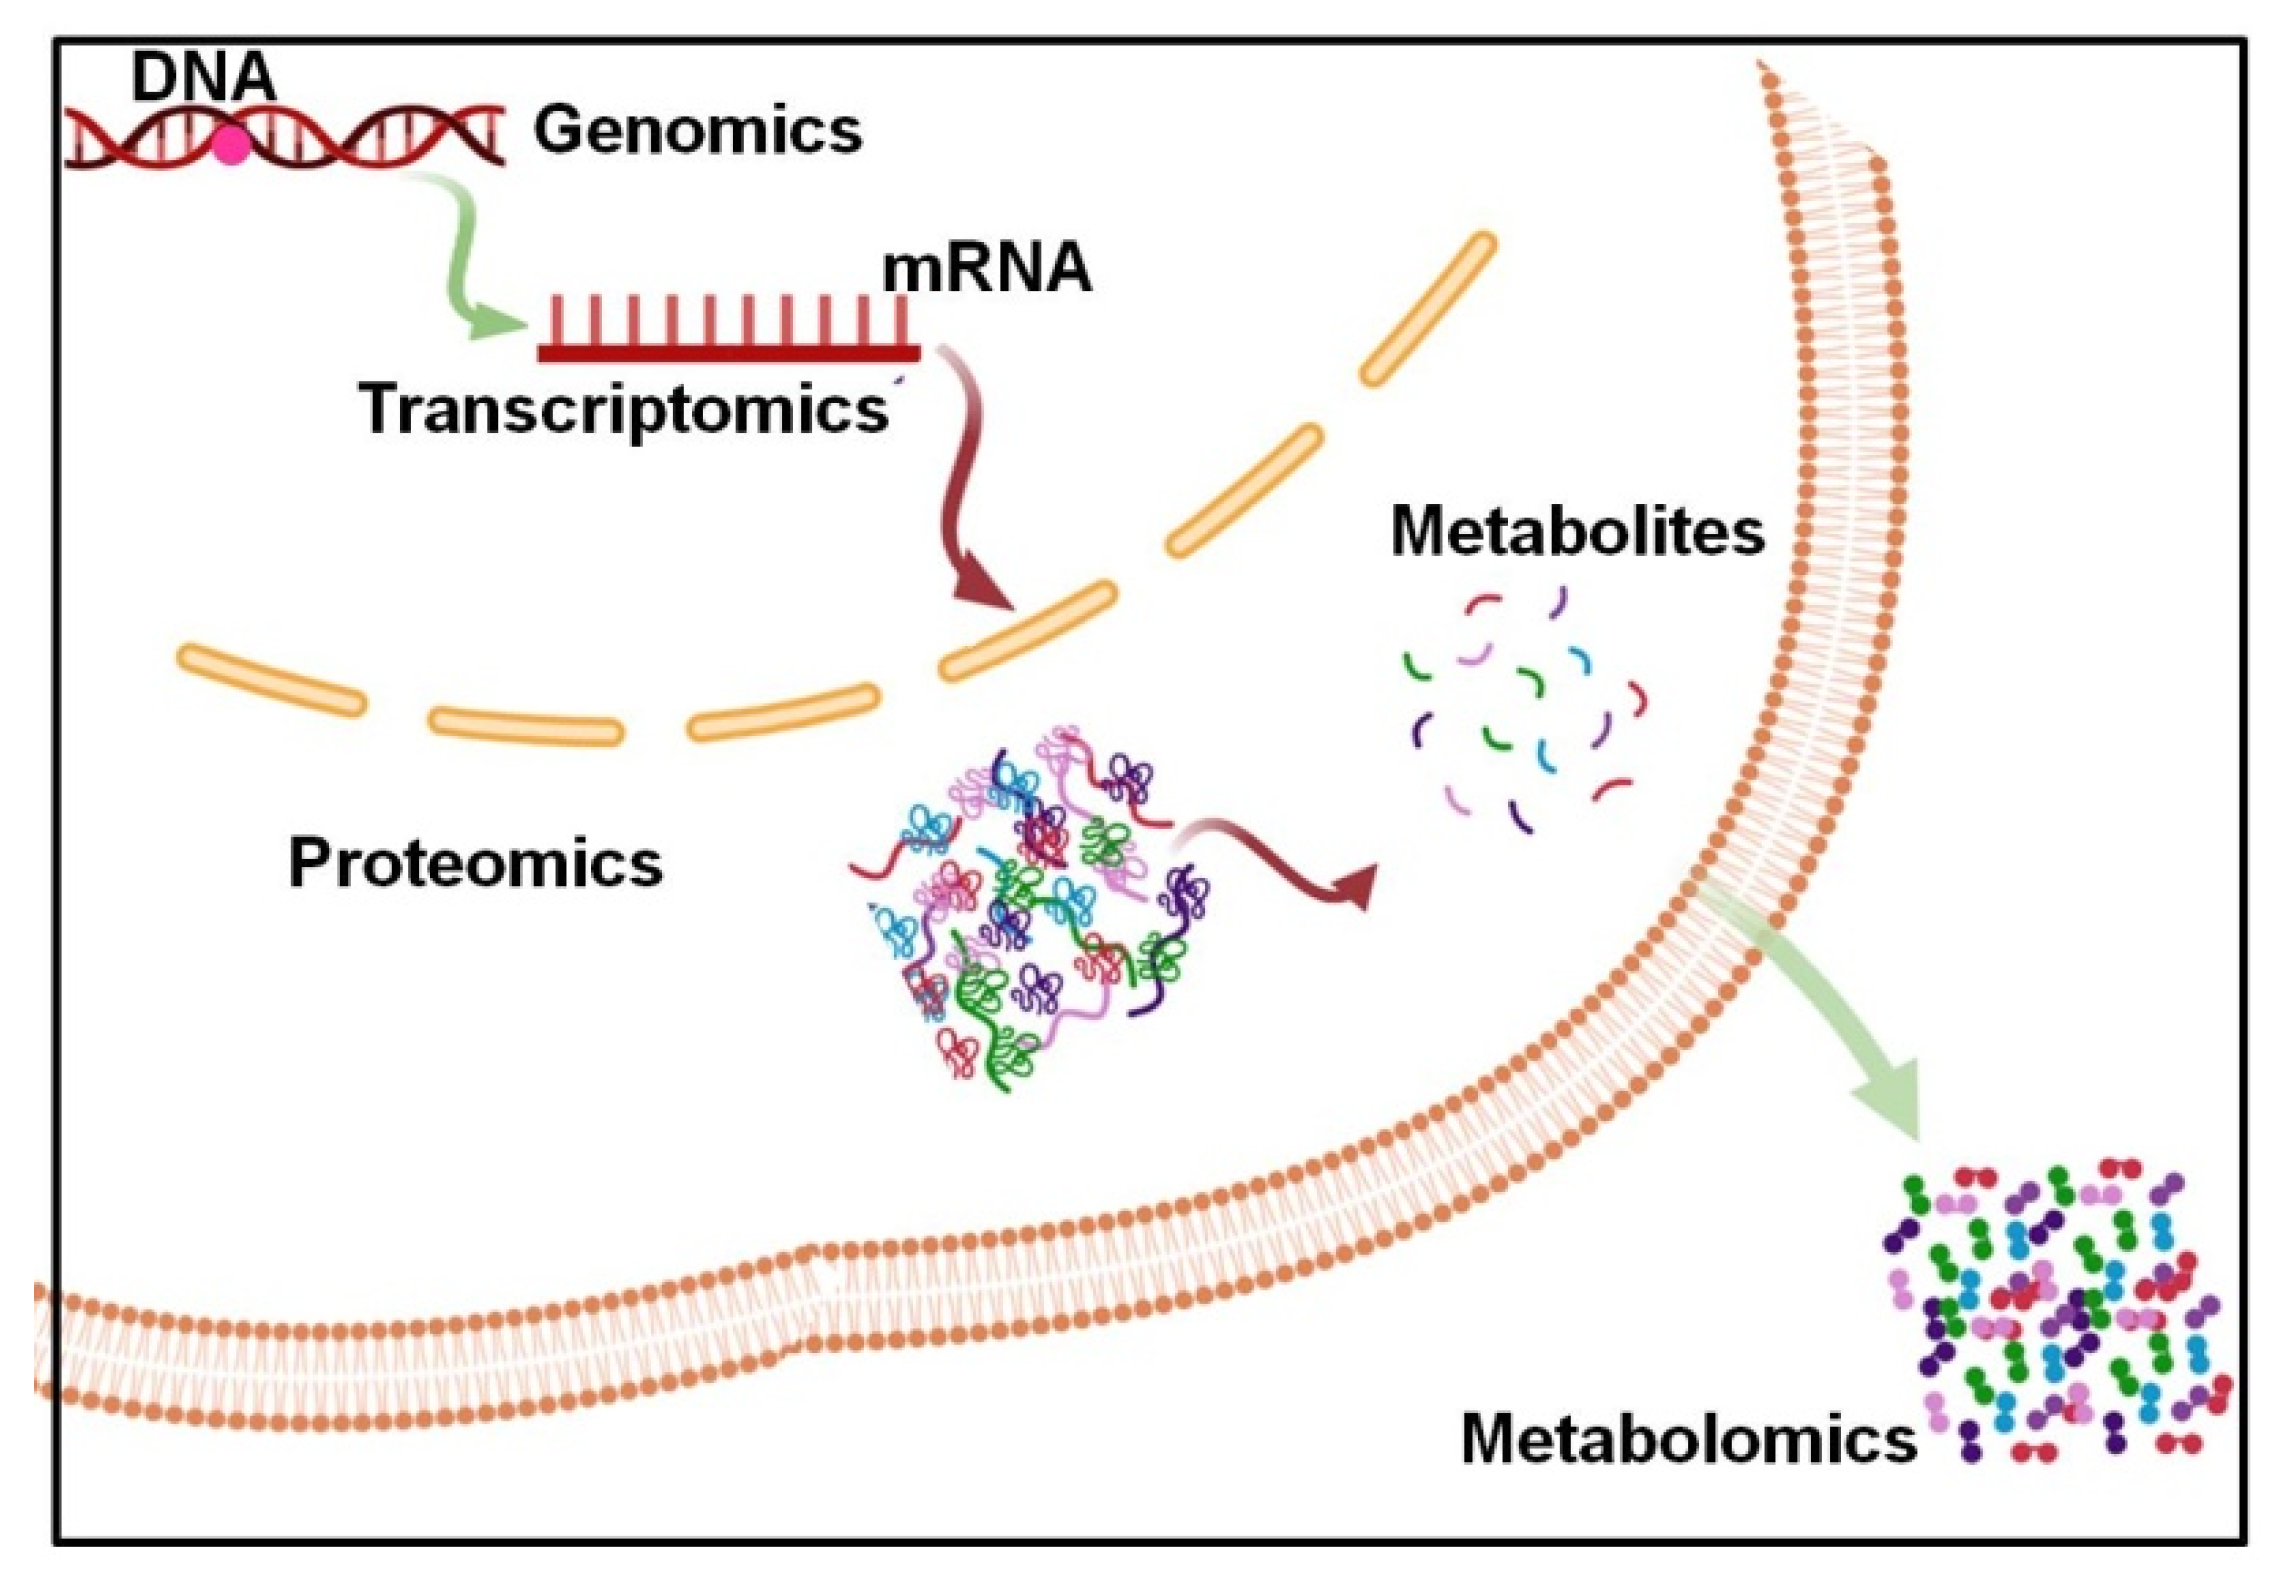

1. Introduction

Cancer Metabolism and Metabolites